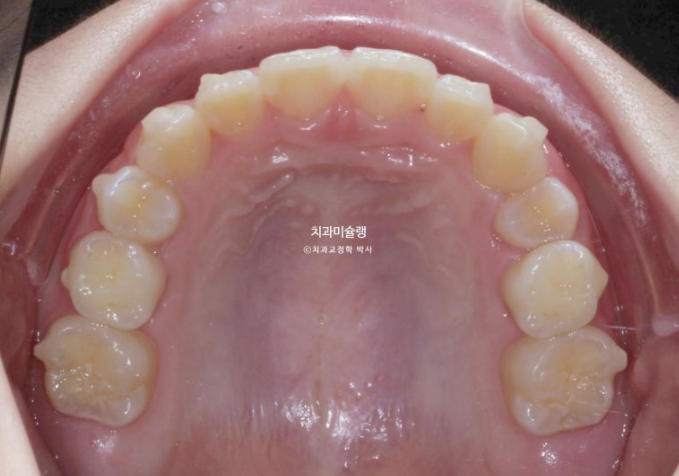

24년 9월까지 6개월간 첫세트 20개 장치를 모두 낀 후 모습입니다.

내려와 있던 가운데 앞니 두 개는 위로 올라가면서 높낮이가 맞아졌고

앞니돌출은 개선이 되었습니다.

그 사이 남아있던 유치가 빠지고 영구치가 잘 나오고 있습니다.

배열은 좋습니다